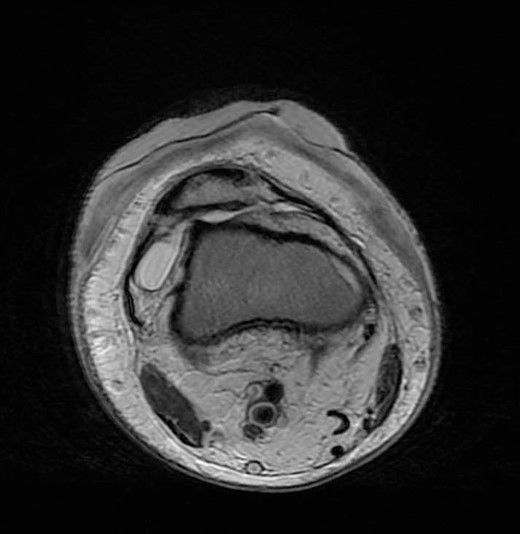

An 18-year-old girl, known case of DEB presented to the emergency department with 1 day history of right knee foreign body sensation, stabbing pain and multiple skin lesion noticed on the same day of presentation. On clinical examination, she had multiple areas of sloughed skin at right knee and leg with multiple furuncular lesions with visible moving larva (Fig. 1). Patient could not do any range of motion of the knee joint due to pain. She was immediately planned for emergency right knee exploration and extensive debridement. Intraoperatively, debridement of the dermis was done, and all visible maggots were extracted as well as larva (Fig. 2). We decided intra-operatively not to expose the knee joint as it seems to be a superficial infestation and is limited to the dermal and part of subdermal layer. Meticulous irrigation was done with normal saline, iodine solution followed by hydrogen peroxide. At the end of the surgery, suffocation therapy was started with application of thick layer of petroleum jelly and it was covered with cotton roll and crepe bandages (Fig. 3). Daily dressing of the lesion was done with the same method of suffocation therapy and no further larva was noticed after 5 days (Fig. 4). Magnetic resonance imaging (MRI) was done and intra-articular extension was ruled out (Fig. 5). Patient was kept on intravenous antibiotic for total of 2 weeks. She was reviewed by physiotherapist for rehabilitation during her hospital stay and the patient was able to ambulate independently before discharge. During her recent follow-up visit after a year, the right knee skin lesion was completely healed and patient was able to bear full weight.

In this case-report, our patient was an 18 year-old and presented with cutaneous furuncular myiasis and was recognized early. Immediate surgical debridement was planned. Initially, intra-articular debridement was also planned but was deferred when limited involvement was noticed. Therefore, it is imperative to have complete knowledge about this condition for planning. In this case, knee joint per se was not affected and was also confirmed by MRI. Hence, opening of knee joint could have led to spread of infection resulted in poor outcome.

The diagnosis of cutaneous myiasis is clinical. There is a punctum at the affected site which represents the entry point of the larva. Though, sonographic assistance can be required in some cases for diagnosis, mostly its avoided as the prognosis depends on the time between presentation and surgical debridement [7]. However, as evident from this case report, the extent of involvement should be clear before deciding the plan of treatment. In areas where there are underlying joints, ultrasound or MRI may help to completely rule out the involvement of joints.